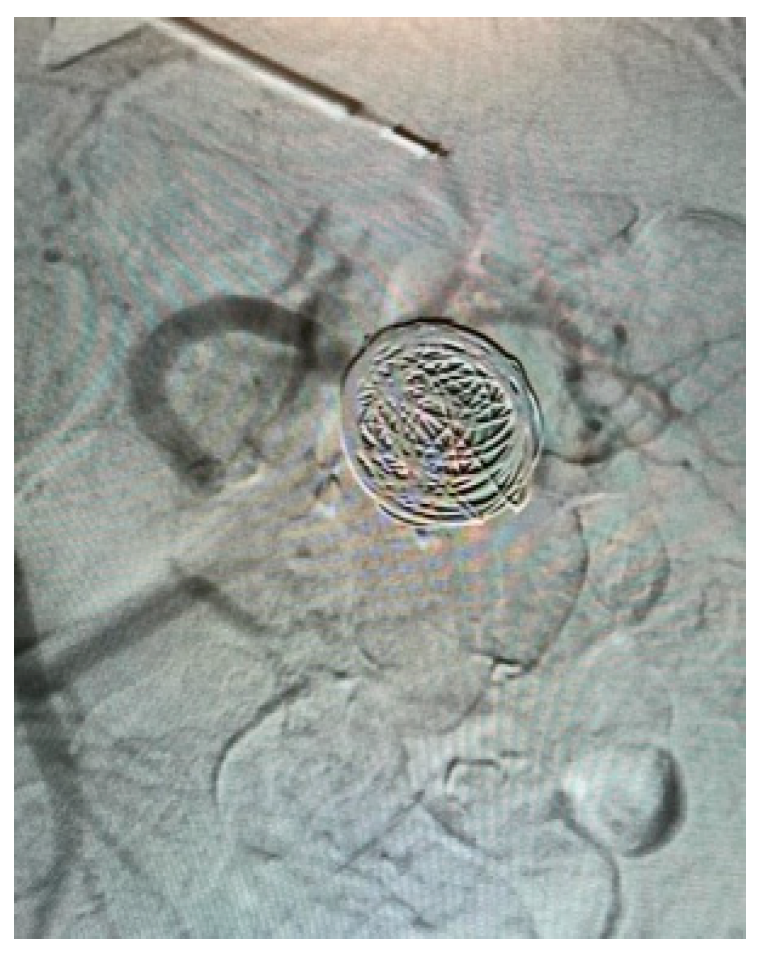

Appendix A.4. Clinical Case 4: Onyx Use in Endoleak Type 1 Excision Post EVAR ABI